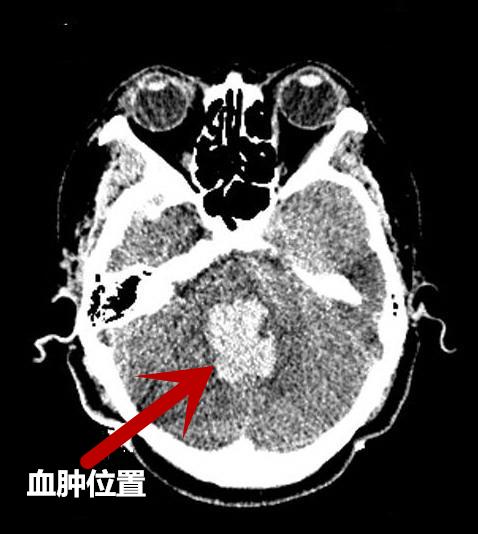

“入院时,患者意识呈深昏迷态势,血压210/116mmHg,自主呼吸急促,面色紫绀,立即行气管插管,呼吸机辅助呼吸,头颅CT提示:脑干出血破入脑室,出血量约13ml,因患者病情危急,转入神经外科ICU给予积极治疗维持生命体征。”接诊的急诊科医生回忆说。

术后复查CT,与术前CT对比血肿明显减少